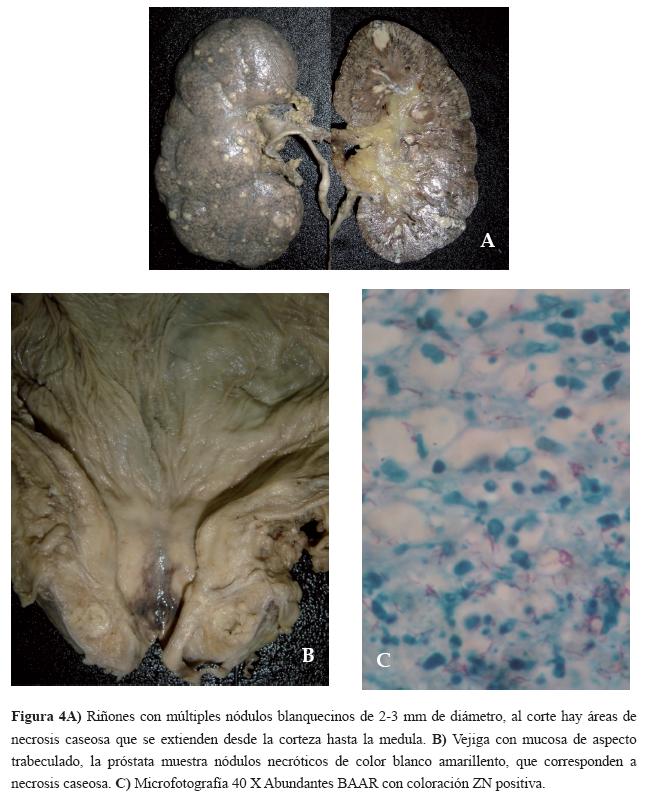

En la autopsia, se encuentra derrame pleural bilateral, ascitis y compromiso tuberculoso de tipo miliar en pulmones, hígado, ganglios linfáticos y meninges. En riñones múltiples nódulos blanquecinos de 2-3 mm de diámetro (Figura 4A) y en próstata nódulos blanquecinos de aspecto necrótico (Figura 4B). El estudio histopatológico muestra inflamación crónica granulomatosa con células gigantes multinucleadas tipo Langhans y necrosis. La coloración de Z.N. muestra abundantes BAAR (Figura 4C).